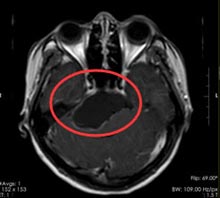

26岁的周女士,20天前出现头晕头痛症状,呈陈发性,休息也缓解不了,有加重趋势,到当地医院检查头颅MR,显示:鞍区巨大占位,考虑颅咽管瘤可能。

在广东三九脑科医院综合神经外科,经鼻蝶鞍神经内镜下行颅咽管瘤切除术,术程顺利,肿瘤全部切除。